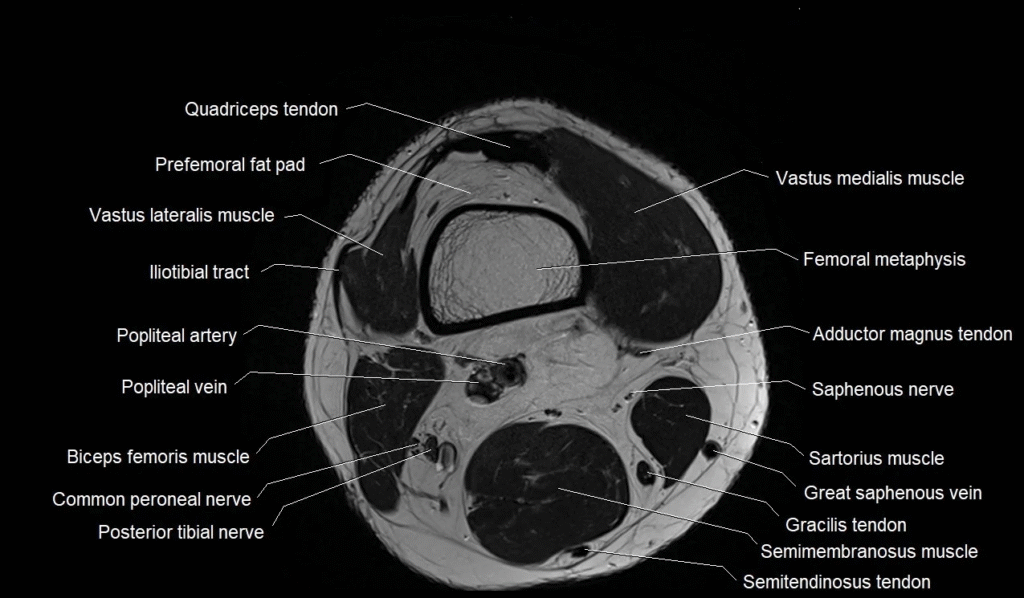

An MRI takes pictures from different angles, showing every important structure in the knee. This includes bones like the femur, tibia, and patella. It also shows soft tissues such as ligaments and cartilage. These details make MRI Knee anatomy helpful for spotting injuries that regular X-rays may miss.

Ligaments keep the knee stable and prevent it from moving in the wrong direction. The knee has four main ligaments: ACL, PCL, MCL, and LCL. These parts are clearly seen on MRI images. If any of them are torn, the knee may feel weak or unstable.

Bones and Joint Alignment in MRI Knee Anatomy